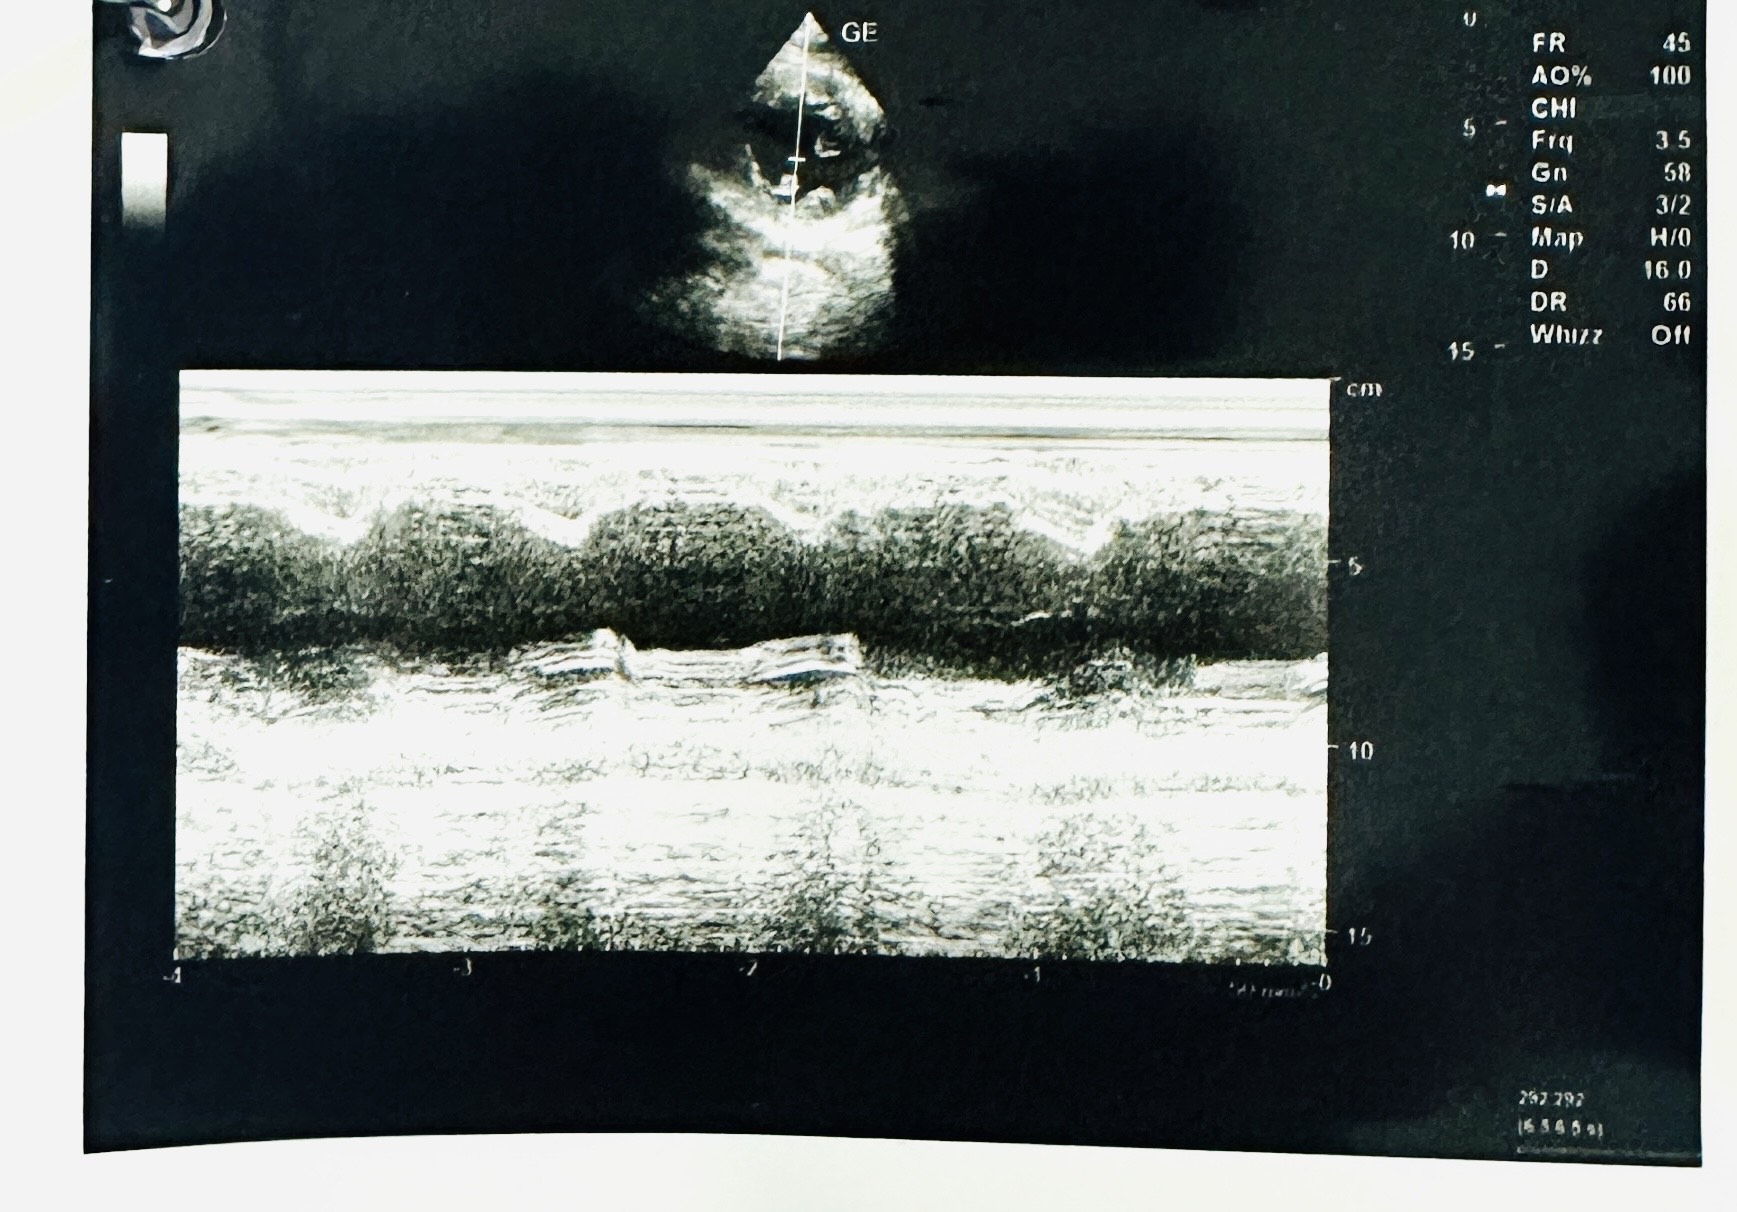

Relevant Test Results Prior to Catheterization

ECG showed Sinus Rhythm heart rate 58 bpm, ST elevation at lead II, III, aVF and Q wave in lead III, aVF and ST depression at lead I, aVL. Diagnosis of Acute ST Elevated Myocardial Infarction Inferior.Echocardiography (TTE) : Mid Inferior wall and Mid Posterior wall are severe Hypokinesia. No pericardial effusion. Primary PCI activated. Chest X ray normal.